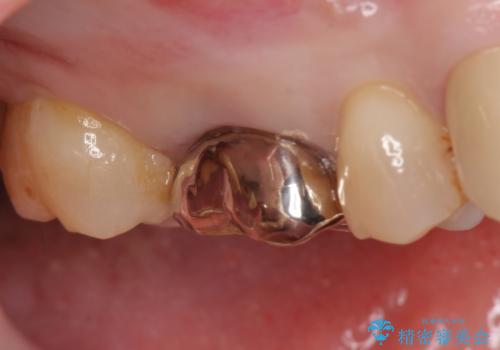

- 右上の奥歯でものを咬むと痛むため他院を受診したが、治療は難しいと言われたため当院にいらっしゃった方の症例です。

再根管治療を行い症状の緩解を確認後、オールセラミッククラウンによる補綴を行いました。